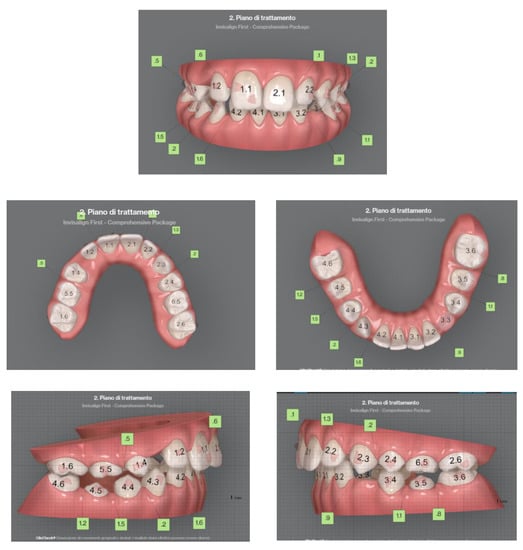

Case 2 concerns a 57-year-old male, with no systemic diseases. He came to our observation in November 2019, to carry out an orthodontic treatment to improve the esthetic appearance of his smile. He showed a good oral hygiene and periodontal condition. Intra-oral evaluation showed a reduction of the transverse diameters, both in the upper and lower dental arches, and a lack of space for the tooth 4.5 in the lower arch (Figure 9 and Figure 10). It was planned to re-establish elements 1.6 and 3.6 after orthodontic therapy in order to reach the first molar class. The most important problem for the patient was related to his smile esthetics and concerned the crossbite of the tooth 2.2.

His specific request was to obtain a noticeable improvement in his smile as soon as possible, with the resolution of the anterior crossbite. It was decided to use aligners to obtain esthetic and functional goals.

Figure 10. Clinical case treated with Invisalign© aligners. Intraoral views from ClinCheck. Frontal, upper, and lower occlusal and lateral view of occlusion before the beginning of treatment.

Sensors 21 01856 g010